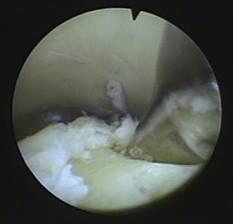

Mikrofrakturierung bei Knorpelschaden am Sprunggelenk

Eine bewährte Technik zur Regeneration des Knorpels im Sprunggelenk ist die Mikrofrakturierung. Dabei wird der unter dem Knorpeldefekt liegende Knochen mit einer Stanze bearbeitet, sodass minimale Einrisse im Knochen entstehen (Mikrofrakturen). Durch die Knochenverletzung kommt es zur Einblutung, dabei strömen Stammzellen aus dem Blut in die defekte Knorpelfläche. Diese Stammzellen differenzieren sich nach einigen Wochen zu Faserknorpel. Der Faserknorpel ist nicht ganz so robust wie der ursprüngliche hyaline Knorpel, erfüllt seinen Zweck zur Auffüllung der Knorpelfläche dennoch sehr gut.